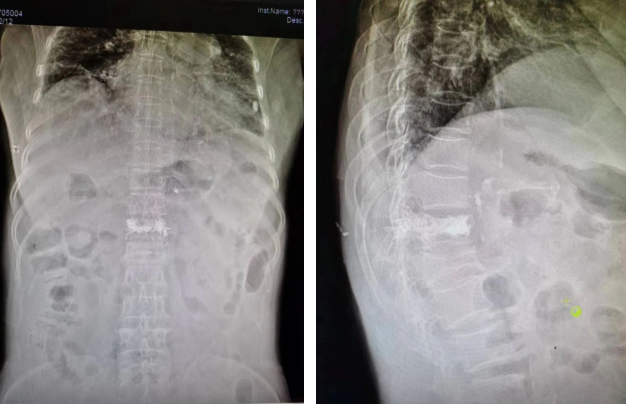

患者入院后,骨科吴郑南医师对患者迅速进行了全面的病情评估,经过反复的研究和积极的术前准备,吴郑南医师决定为患者实施经皮穿刺椎体成形术(PVP)。完善各项术前准备,7月4日,在吴郑南医师和骨科医疗团队的共同努力下,成功完成了手术。患者术后疼痛基本明显减轻,第三天便可坐立,并且在家人的搀扶下可下床活动。出院后第五天,相关医师回访了解到患者已经可以自行下床活动行走,疼痛基本消失。患者及家人非常满意!